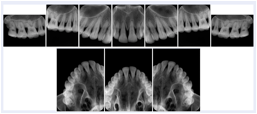

2. A patient requests cosmetic surgery to enhance their facial appearance. The case requires consultation between an orthodontist in New York and an oral surgeon in California. The cephalometric series of 2D projections constructed from a volumetric CT data set that is used for the discussion is arranged by a Structured Display for transfer between the two practitioners.

Cephalometric Series Structured Display

Figure OO-2. Cephalometric Series Structured Display